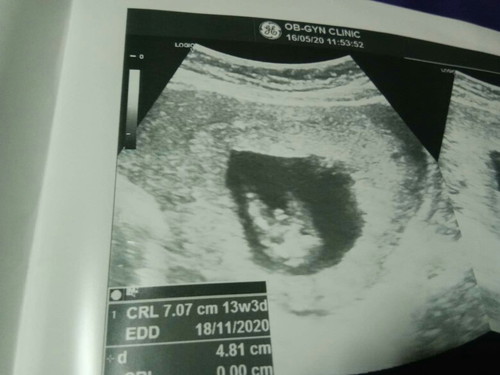

ช่วยดูหน่อยค่ะว่าผู้หญิงหรือผู้ชาย ตอน13วีคหมอบอกผู้ชาย แต่อยากให้คอนเฟิร์มหน่อยน่าาาว่าชายจริงๆ อิแม่อยากได้ชาย

อาจเปลี่ยนแปลงได้20สัปดาห์ค่อยชัดเจนค่ะ